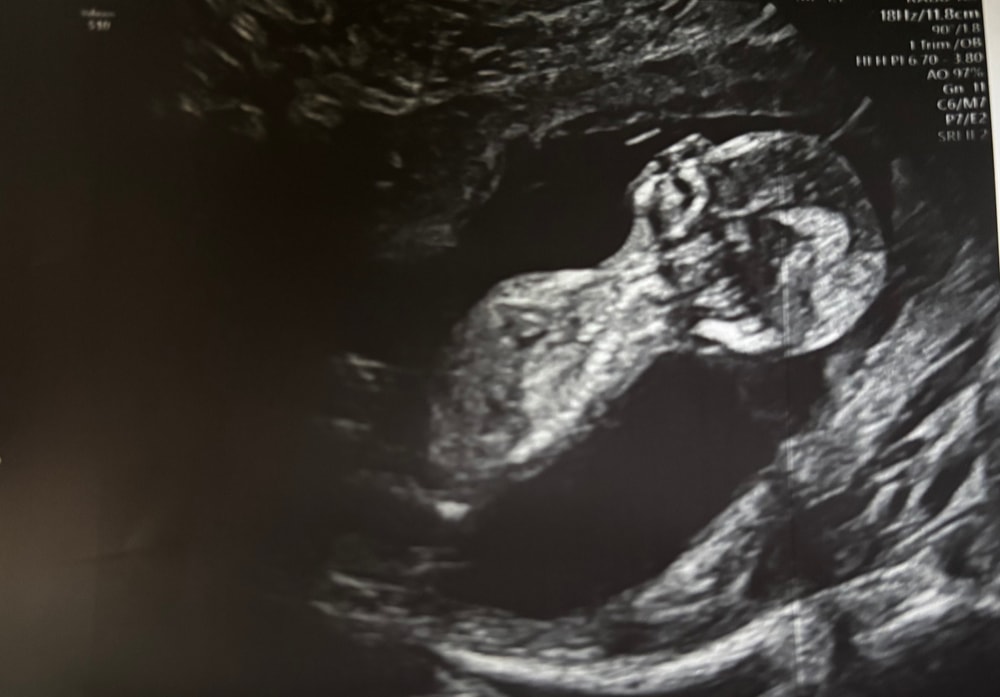

Узи 13 неделя

Здесь 12+6 🩵 Изображение